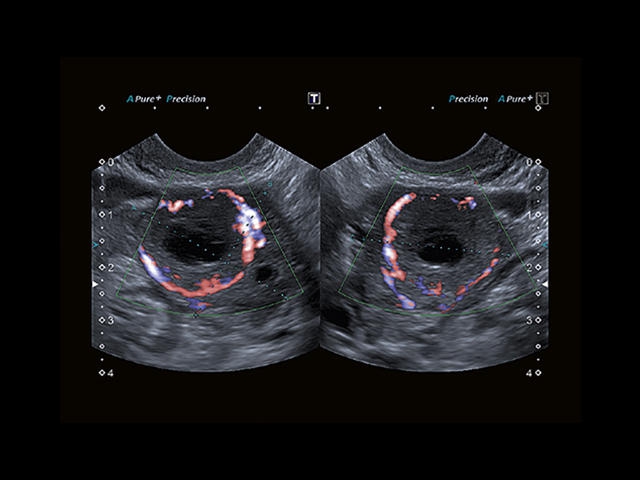

Aplio 500 – ультразвуковой сканер премиум класса, сочетающий в себе быстродействие диагностики и отличное качество визуализации. Более 30 датчиков на выбор, в т.ч. матричные, монокристаллические, 4D, эндоскопические для любых типов исследований. Ультразвуковой сканер позволяет изучать анатомические структуры в высоком разрешении.

Обновленная версия легендарного УЗ-сканера. Стационарный аппарат экспертного класса Aplio 500 Toshiba NEW, визуализирует анатомические структуры в высоком разрешении. Модель позволяет выявить микрокальцификаты, новообразования, нарушения в работе сердца, сосудов и мышц. Присутствует функция виртуальной эндоскопии, 4D-сканирования, эластометрии тканей, УЗИ с контрастированием. За повышение качества изображения отвечают технологии ApliPure и Superb Microvascular Imaging. Первая задействует возможности пространственного и частотного кодирования, формирует цельный визуальный ряд с сохранением клинических маркеров. Вторая улучшает отображение микрососудистого русла, используя доплеровский эффект. Модель оснащена 21-дюймовым монитором, имеет 4 активных порта. Возможно подключение педиатрических, интраоперационных, лапароскопических и чреспищеводных датчиков.

• SMI. Опция, упрощающая визуализацию микроциркуляторного русла. С ее помощью обследуются сосуды с низкой интенсивностью кровотока, изучаются наиболее тонкие структуры. SMI упрощает диагностику новообразований, минимизирует вероятность ошибки.